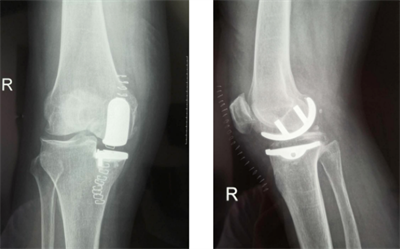

(图示膝前内侧骨关节炎X线及术中情况)